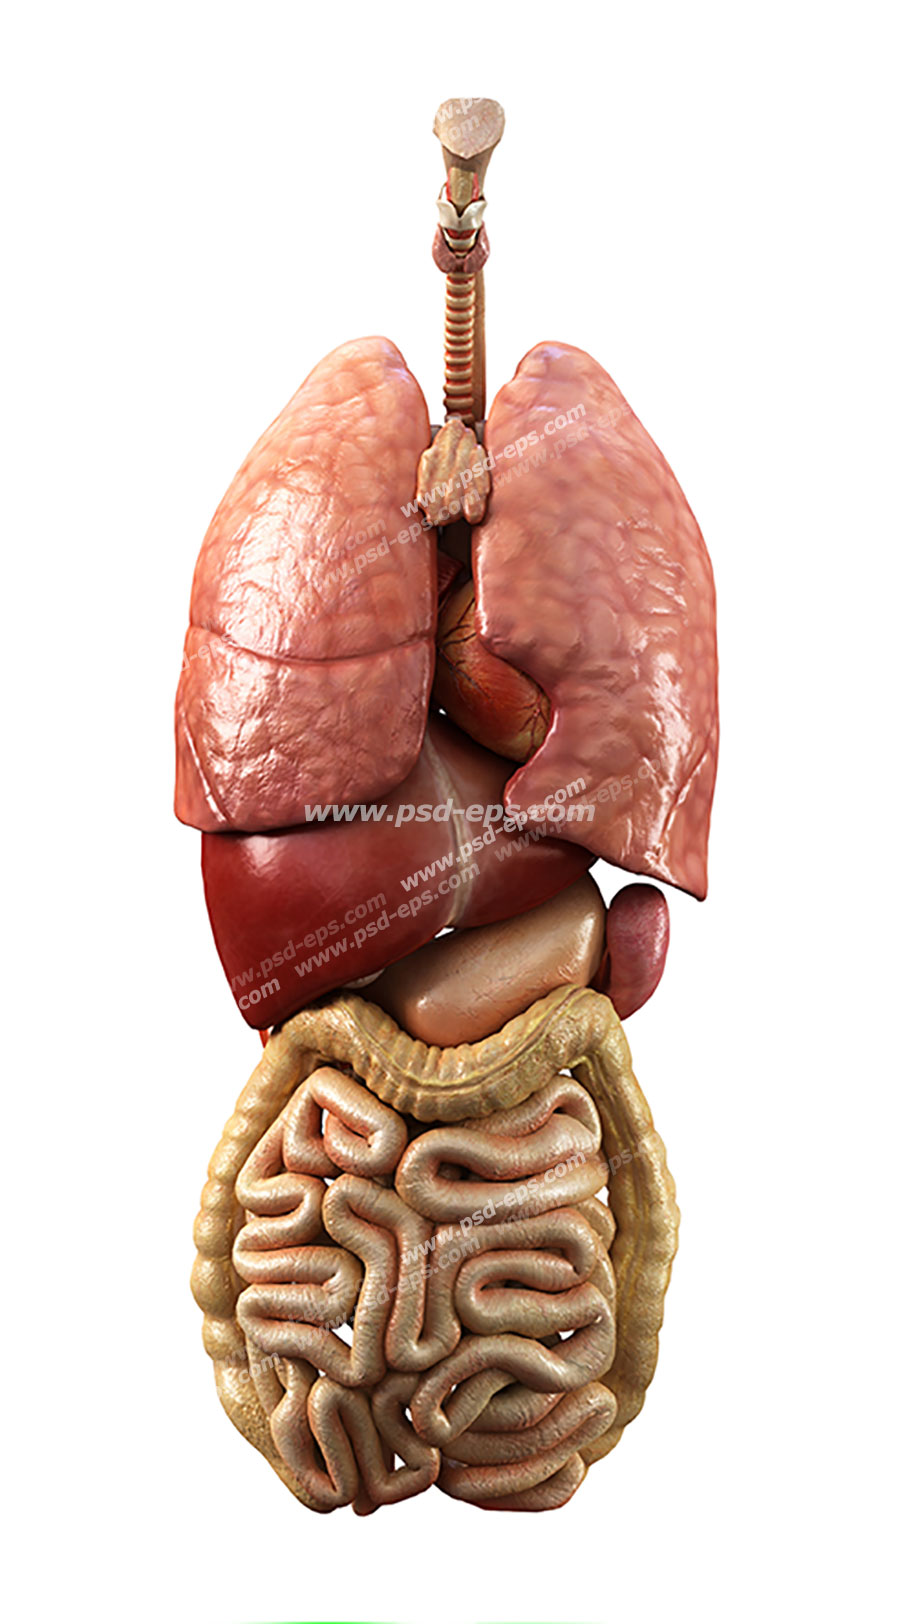

عکس داخل شکم انسان. در این همان طور که مشخص است شکم حالت بیضی شکل پیداکرده و این بیضی که کناره های شکم کشیده شده است. تعداد سلول های بدن انسان حدود ۳۷ ۲ تریلیون تخمین زده شده اند. Abdomen که در زبان عامه به غلط به آن دل نیز می گویند در آناتومی به قسمتی از تنه گفته می شود که مابین دیافراگم از بالا و سطح فوقانی لگن خاصره از پایین قرار دارد. ربات دیدنی ربات انساننمای چینی به صورت یک دختر جوان ساخته شده و جیا جیا نامگذاری شده است این ربات طوری برنامهریزی شده که میتواند صحبت کند و احساسات خود را از طریق تغییرات در چهره حالات.

شکل دوم شکم مادری را نشان می دهد که جنین دختر دارد. وحشت مادر از عکس سونوگرافی جنین داخل شکمش عکس. تصاویر جالب از داخل مغز و نخاع انسان آخرین نیوز. بدن انسان کل ساختار انسان است که سر گردن تنه سینه و شکم دو بازو و دست ها و دو ساق پا و پاها را شامل می شود.